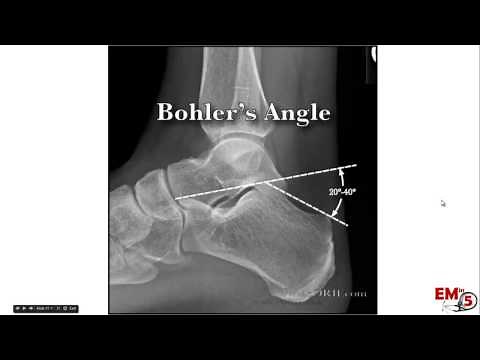

Fraktur